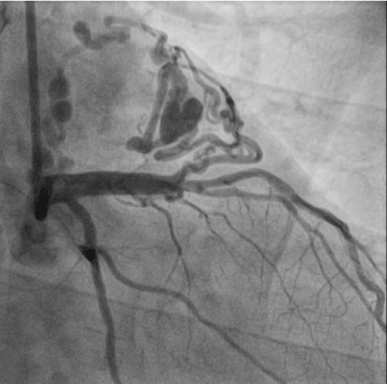

A 59-year-old man presented to the outpatient clinic of cardiology department with recurrent chest pain for several weeks. An electrocardiogram showed sinus rhythm with T wave inversion in leads V2 through V6, and appearance suggestive of anterior-wall ischemia (Figure 1). Two-dimensional transthoracic echocardiography showed no regional wall motion abnormality. Elective coronary angiography was performed. Very tortuous and dilated fistula track originated from left main stem linked to ‘heart-shaped’ small chamber and drained to right atrium on various projection views (Figures 2-4). He was referred for surgical obliteration of the fistula. After surgery, he suffered from postoperative myocardial infarction and heart failure. With ongoing medical conservative treatment, the chest pain and dyspnea resolved within 2 weeks, respectively and discharged. He was discovered with state of death in his home at follow-up 3 months later. The cause of death is not known but suggestive of sudden cardiac death. Perioperative myocardial infarction is an important complication of ligation of coronary artery fistula and could contribute to his sudden death.

Figure 3. Coronary angiogram with right oblique view